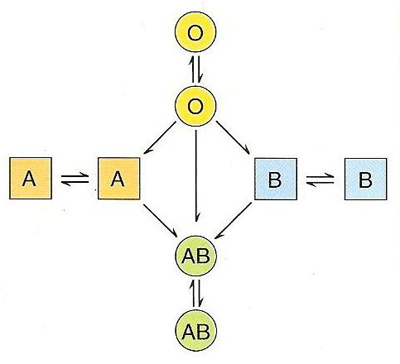

A expressão fenotípica das formas alélicas, que determinam o grupo sanguíneo de um indivíduo, resulta na presença de antigénios A e/ou B na membrana das hemácias e anticorpos no plasma (anti-A ou anti-B). O tipo sanguíneo O não apresenta antigénios na membrana das hemácias mas apresenta ambos os anticorpos no plasma. O tipo sanguíneo AB apresenta ambos os antigénios na membrana das hemácias, mas não contém anticorpos no plasma. Estas características vão determinar a compatibilidade ou incompatibilidade sanguínea, uma vez que se estiverem presentes o mesmo tipo de antigénio e anticorpo, as hemácias vão aglutinar com os anticorpos. O processo de aglutinação consiste na reação entre um anticorpo presente ou produzido no plasma (aglutinina) e os antigénios presentes na membrana das hemácias (aglutinogénio), formando um aglomerado de pequenas massas de células. Por esta razão, o portador do tipo sanguíneo O é um dador universal e o portador do tipo sanguíneo AB é um recetor universal (figura 3).

Assim, é muito importante que as transfusões sanguíneas sejam feitas com a maior segurança para o paciente, para prevenir incompatibilidades entre o sangue do dador e do recetor, sendo necessário determinar os seus grupos (sistema ABO) e tipos (fator Rh). A compatibilidade entre dador e recetor é fundamental para a segurança transfusional.

Figura 3 – Compatibilidades entre os grupos sanguíneos do sistema ABO